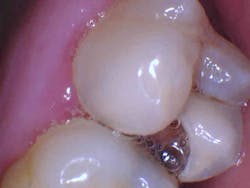

In the case below, tooth No. 2 was diagnosed with symptomatic irreversible pulpitis and symptomatic apical periodontitis with a mesial marginal ridge fracture due to extensive caries (figure 1). Root canal therapy and a full coverage crown were recommended and the patient accepted.

The carious tissue was removed, followed by the endodontic procedure and subsequent placement of the build-up. Despite the deep extent of mesial decay, a clear and accurate scan was achieved (figure 2).